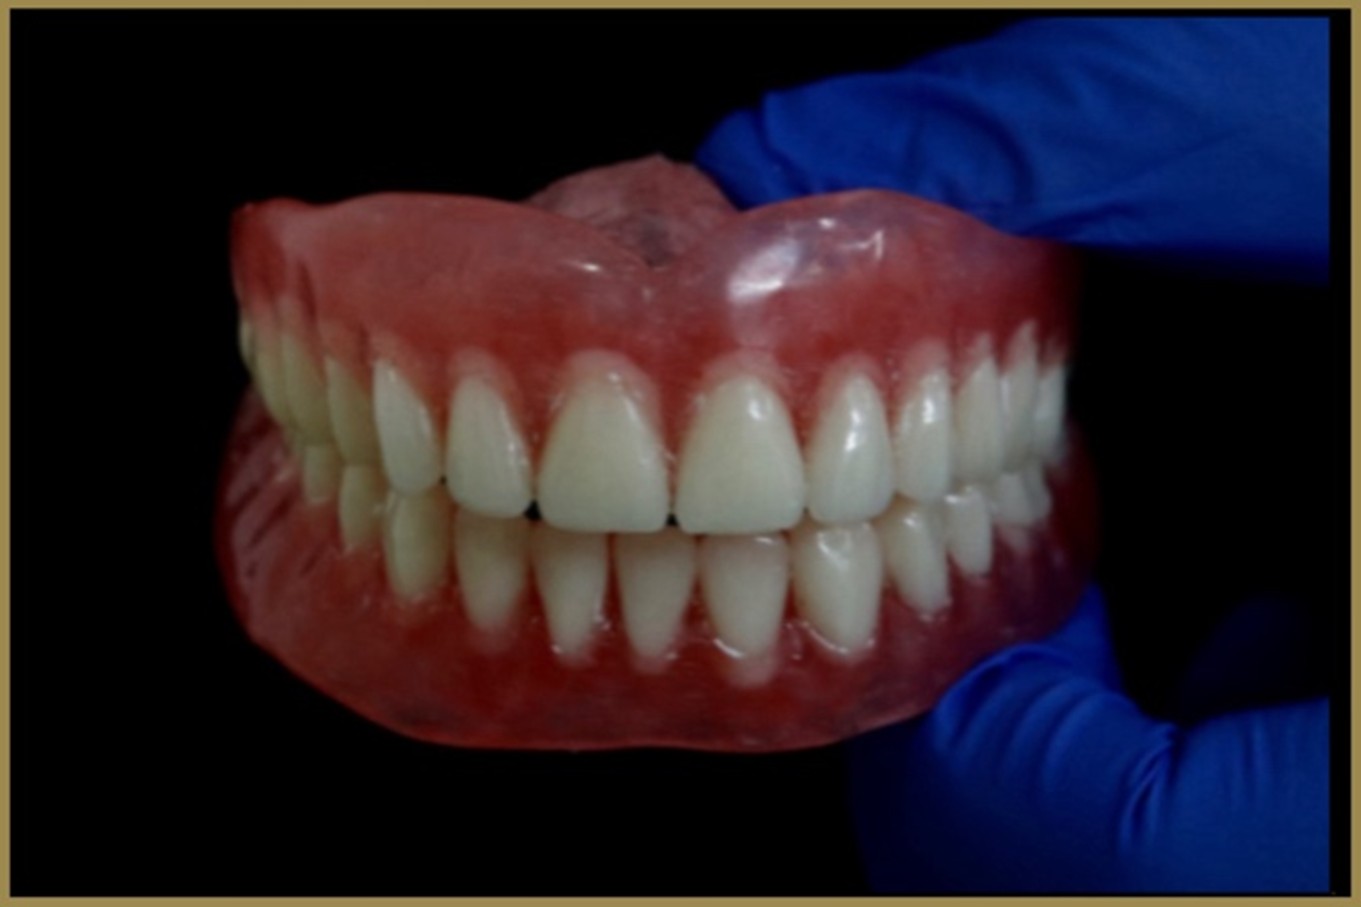

From preventive care to orthodontics, implants, cosmetic dentistry, and digital treatments.